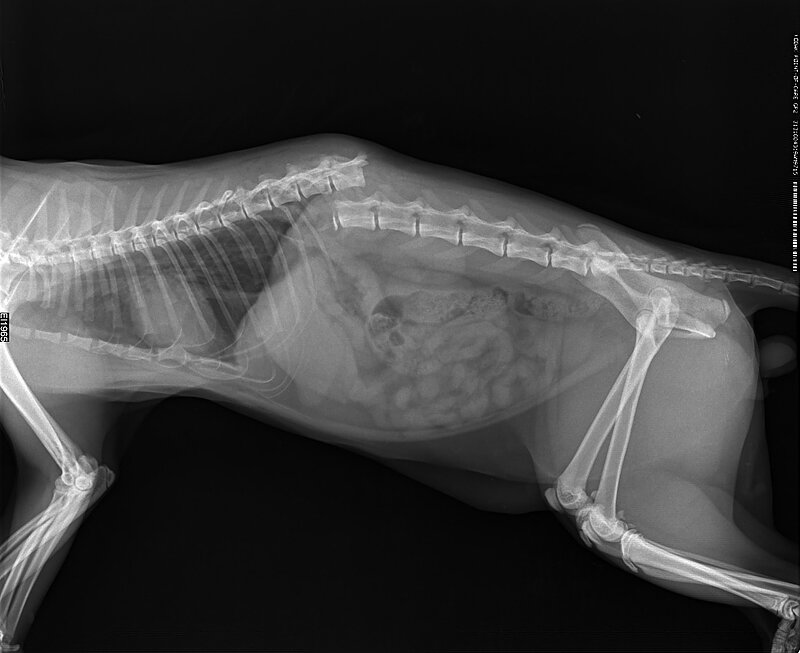

Чаще всего ветврачи регистрируют следующие травмы: ⠀

1. Переломы и ушибы: ⠀ ⠀

1. Переломы и ушибы:

• конечностей;

• позвоночника;

• таза;

• ребер;

• основания хвоста;

• челюсти;

• трещина верхнего неба. ⠀

За фото благодарим ветврачей из клиника

"Эпиона" и ветврача Михаила Шелякова